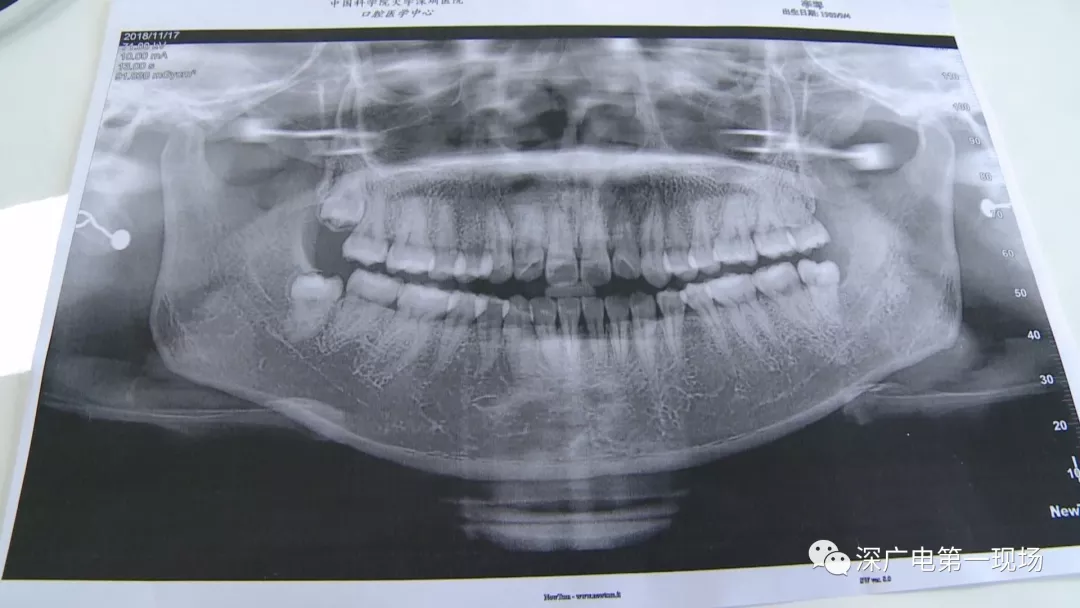

中國科學(xué)院大學(xué)深圳醫(yī)院口腔科主任賈岳介紹,對(duì)于不同患者的牙齒,它的治療方法都不一樣,所以不同牙齒,醫(yī)院收費(fèi)的標(biāo)準(zhǔn)也各不相同。牙齒的治療方案,都是根據(jù)患者牙齒具體情況來制定,然后再去收費(fèi),同時(shí)也會(huì)參考病人實(shí)際情況來做不同的治療項(xiàng)目。